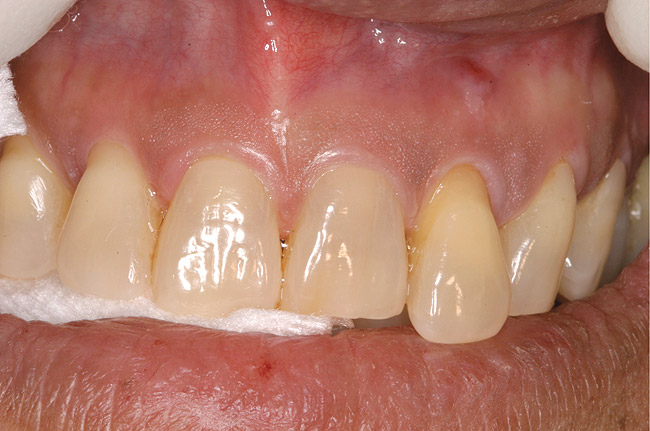

Figure 17  Supraeruption of tooth No. 10 and healing fistula in the apical area.

Figure 17

Figure 18  Same case as in Figure 17 after extraction of tooth No. 10 and immediate implant placement (Astra Tech, Inc, Waltham, MA) with delayed restoration. Note the significant coronal position of the soft tissue.

Figure 18

Figure 19  Radiographic view of the case seen in Figure 18.

Figure 19

Figure 17 shows a case of advanced recession on the facial of tooth No. 10, which had a periodontal-endodontic lesion. Tooth No. 10 was extracted with an implant placed during the same appointment. As demonstrated in this case (Figure 18 and Figure 19), the facial gingival margin can be moved coronally with immediate implant placement.